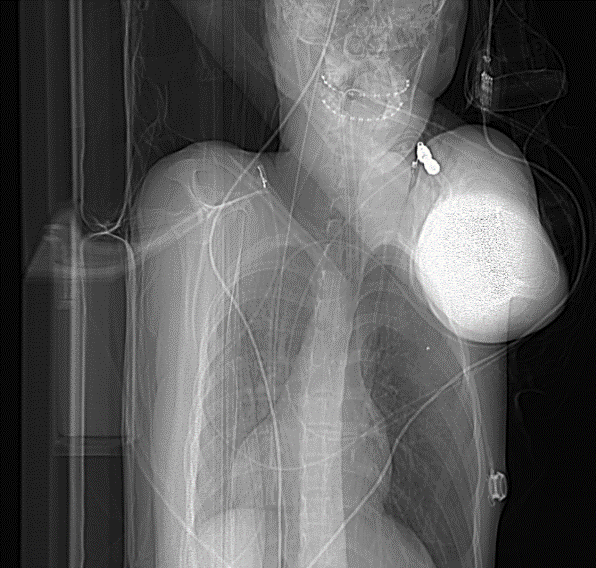

Figure 3: Arrow showing coil on scanogram